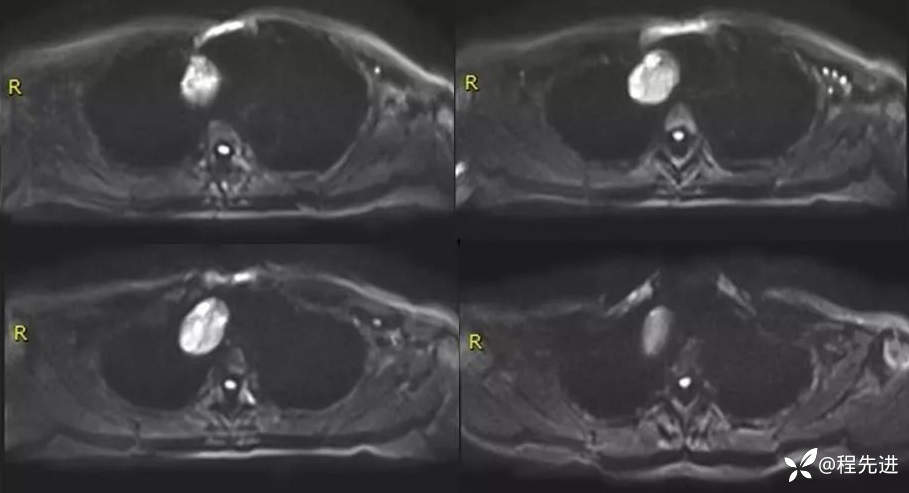

MR

DWI

ADC